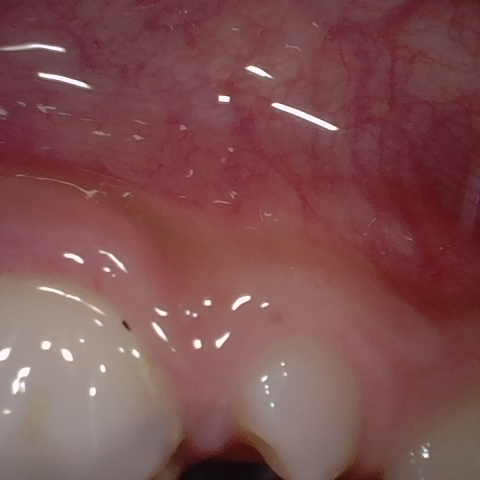

Annotated as "Good"